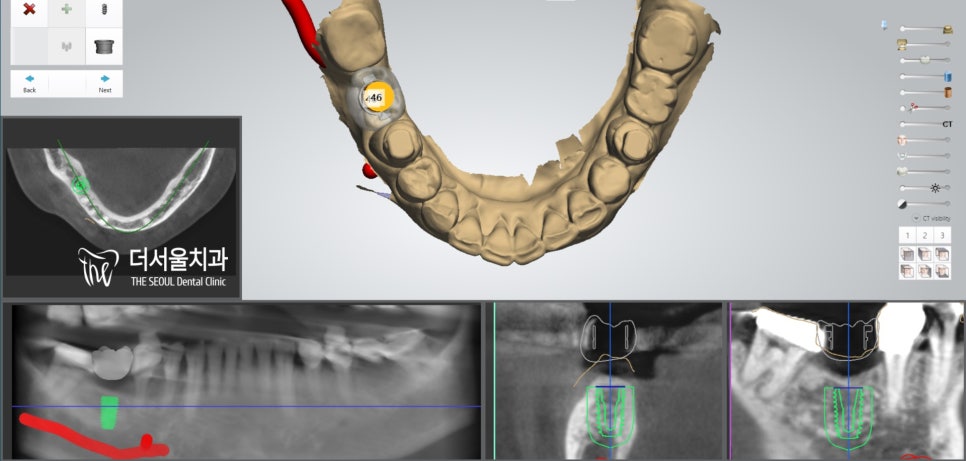

『46번 디지털 임플란트 ,

45번 47번 크라운 재제작』

『디지털 임플란트 및 크라운 재제작 증례』

디지털 임플란트 는

컴퓨터 분석을 통해

조직, 인접치와의 거리를

상세히 파악해 줍니다.

기존 방식보다

더 정확하고 안전한 식립이

가능하다는 뜻이죠.